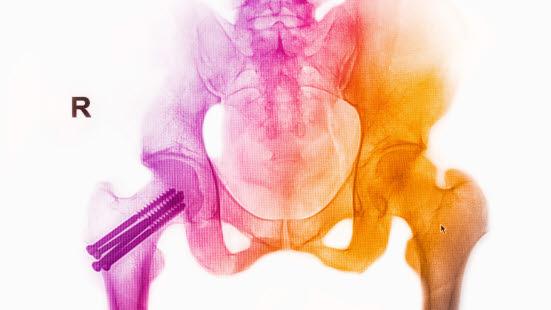

Oversikt lår, hofte, bekkenLårbeinet (femur) består av leddhodet, lårhalsen, trokanterområdet, skaftet og kondylene i kneleddet. Leddhodet (caput) er kuleformet og ligger inne i en halvmåneformet leddskål i hoftebeinet (hofteskålen eller acetabulum). Lårbeinet har en vinklet form. Fra hofteskålen i bekkenbeinet går lårbeinet skrått utover ca. 10 cm før det vinkles rett nedover. Partiet fra leddhodet og til der lårbeinet vinkles nedover, er lårhalsen. Vinkelområdet kalles trokanter.

Lårhalsbrudd innebærer som navnet sier, et brudd på lårbeinets lårhals (forekommer hos 55 prosent) eller i trokanterområdet (45 prosent). Avhengig av hvor lårbeinet brekker, inndeles hoftebrudd i flere undertyper (se figurene nedenfor). Den viktigste inndelingen er at det skilles mellom brudd med og uten feilstilling (dislosering).

Ved brudd uten feilstilling er det enighet om at behandlingen skal være skruer eller nagler uansett alder. For brudd med feilstilling, derimot, anbefales det hos eldre pasienter å sette inn protese (gjøre leddplastikk). Dersom pasienten har hatt plager med hofta før skaden skjedde, settes det inn halvprotese (bare leddhodet skiftes). For friskere eldre settes inn totalprotese (skifter både leddhode og leddskål). Om det foreligger hofteleddsartrose (slitasjegikt), skal pasienten også ha totalprotese. I Norge brukes hemiproteser i over 90% av primære proteseoperasjoner ved akutt hoftebrudd

Unge, friske pasienter under 60-65 år bør behandles med skrue og/eller nagler (osteosyntese) uavhengig av grad av feilstilling.